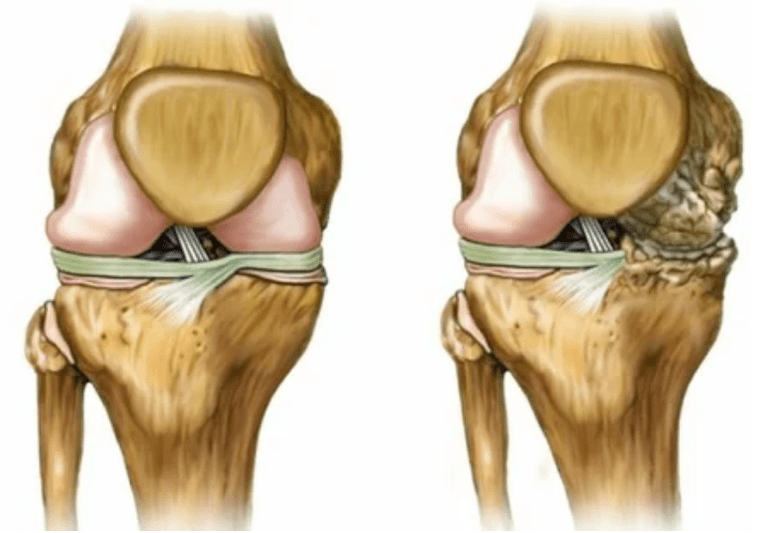

- 3 degrés. Il y a souvent de la douleur, il est difficile de déplacer le membre en raison de changements dans l'articulation. Les lésions sont étendues et sont perceptibles pour le look nu. La déformation de la position articulaire se produit, la zone affectée gonfle et devient rouge. L'axe des membres est perturbé, ce qui conduit à la complexité du mouvement. Les ligaments produisent des changements pathologiques. Les sous-exemplaires et les contractures apparaissent. Les muscles adjacents sont raccourcis ou étirés à partir desquels la fonction contractile est affaiblie.

Membres limités. Si apparaît sous une forme négligée de la maladie, la destruction complète du tissu du cartilage et l'occurrence des ostéophytes indiquent. Dans cet état, la pression augmente sur les joints en haut et en dessous, à partir de laquelle la courbure peut affecter l'ensemble de la liaison.

- L'articulation est complètement détruite;

- Le membre est immobilisé, tous les mouvements sont extrêmement difficiles;

- Forte déformation de l'articulation ou du membre entier.